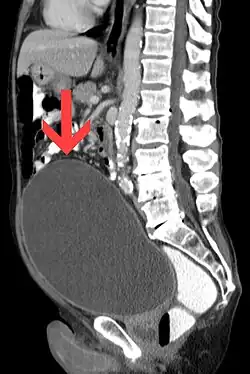

![]() | |

Urinary retention with greatly enlarged bladder as seen by CT scan. | |